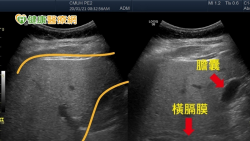

70歲賴伯伯最近經常腹瀉、腹脹,嚴重時還有血便情形,忙碌或壓力一來症狀更是嚴重,自行到藥局購買止瀉藥服用仍未改善,其症狀反覆已有一個多月,甚至出現疲倦無力情形,體重也急遽下降,家人趕緊將其送至急診就醫,檢查後發現賴伯伯白血球指數上升及電解質不平衡,最終排除感染性腸炎,診斷為左側「潰瘍性結腸炎」。 潰瘍性結腸炎成因未明 基因、環境、飲食都有影響 臺中榮總嘉義分院大腸直腸科醫師陳昌...... [閱讀更多]